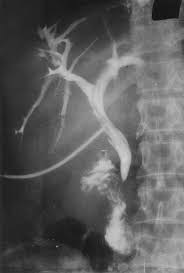

- Cholangiographie

transhepatique per cutanee : La cholagiographie

trans-hepatique est une radiographie des voies biliaires en

injectant directement dans le voie biliaire un produit de

contrast radio-opaque . Cela est possible nul que si elles

sont dilatees . La technique soit realise par une perfusion et

une injecte de calmant ,et anesthesie locale .Voie

d'abord est sur la ligne axilaire mediane ,au dessous de cul-de

sac pleural et dirige en direction vers le col de la 11e

cote . , on injecte le produit de contrast hydrosoluble et

prend les cliches imediatements . On peut utilisee le guide

de aiguille pour instalee une petite catheter pour drainage

la bile qui est en bloquee par un obstacle

. Technique se donne des images tres net des voies

biliaires intrahepatique i

| |

|

Par une aiguille avec catheter place

a une des branche de voie biliaire le produit de

contrast a injecte suffisament pour opacifie

de tous le voie biliaire |

Voie d'abord est sur la ligne axilaire ,

au desous de cul de sac pleurale , dirrige vers le

col de la 11eme cote droit |

Image radiologique de voie

biliaire intrahepatique dilate . La vesicukle

biliaire , le canl cystique et canal choledoque sont

en vue nette . Cholagiographie per cutanee |

Images cholagiographies par

drain de Kehr . Les branches de voie biliaire sont

en vue |

Les indications de

cholangiographie per cutanee : Tous les

causes de blocages de voie biliaire qui se donne la

retention biliaire |

peroperatoire et cholangiographie par drain de Kehr :

Comme le technique radiologique de cholangiographie per

cutanee , le produit de contrast doit injecte en

direct au canal choledocque per-operatoire ou

post operatoire par drain Kehr permet d'opacifier les

voies biliaires extra et intrahepatique permet de verifie

l'integrite des voies biliaire et la reste des calculs

inconnue

Cholangiographie par drain de Kehr |